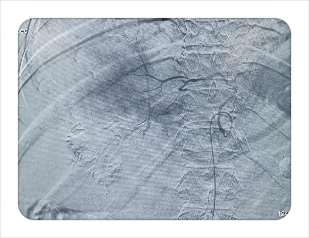

同时,在医技护及家属的协同下,通过放射科绿色通道患者在短时间内完善了腹部急诊CT检查,结果显示:右肝巨块型肝癌破裂出血伴腹腔积血。迅速完善术前评估,告知家属患者病情危重需行急诊介入手术,家属表示同意并签署手术同意书,随即推入DSA手术室。闻讯赶来的放射介入团队接过病人后在梁琪主治医师的带领下迅速行经导管肝动脉造影+栓塞术。术中造影证实患者右肝VI段区域一破裂出血肝动脉分支,立刻行微导管插管,予以PVA颗粒超选择性栓塞,再次造影后右肝VI段出血动脉未见明显显影,且未见异位栓塞征象。术后患者生命体征平稳,安返病房。